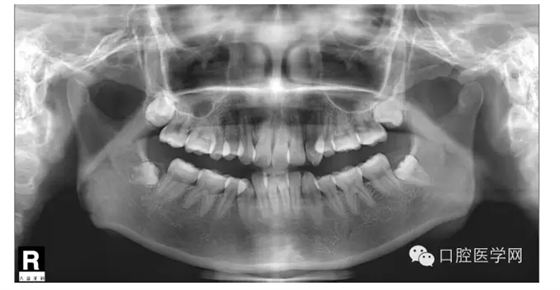

這是一位我同事接診的一位患者,成年女性,安氏II類,高角,下頜后縮,重度深覆合,上下中線右偏,原本做過一次矯正,4個4已經(jīng)拔除。

我同事又給她拔了左邊兩個5,然后我同事離職了,把患者扔給我。

這個患者,II類高角,下頜后縮,所以我們不能抬高磨牙,另外兩個上頜中切牙牙根短小,也不能大幅壓入。

所以這個患者我選擇使用弓絲壓低下前牙。但由于雙尖牙只剩下15,45,所以我們將37,47,納入矯正。